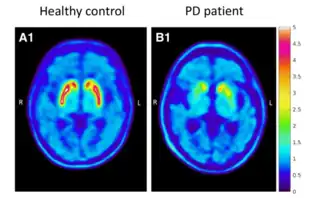

Imaging

Diagnosis can be aided by molecular imaging techniques such as magnetic resonance imaging (MRI), positron emission tomography (PET), and single-photon emission computed tomography (SPECT).[142] As both conventional MRI and computed tomography (CT) scans are usually normal in patients with early PD, they can be used to exclude other pathologies that cause parkinsonism.[141][143] Diffusion MRI can differentiate PD from multiple systems atrophy (MSA).[144] Emerging MRI techniques of at least 3.0 T field strength—including neuromelanin-MRI, 1H-MRSI, and resting state fMRI—may detect abnormalities in the substantia nigra, nigrostriatal pathway, and elsewhere.[141]

Unlike MRI, PET and SPECT use radioisotopes for imaging.[145] Both techniques can aid diagnosis by characterizing PD-associated alterations in the metabolism and transport of dopamine in the basal ganglia.[146][147] Largely used outside the United States, iodine-123-meta-iodobenzylguanidine myocardial scintigraphy can assess heart muscle denervation to support a PD diagnosis.[148]